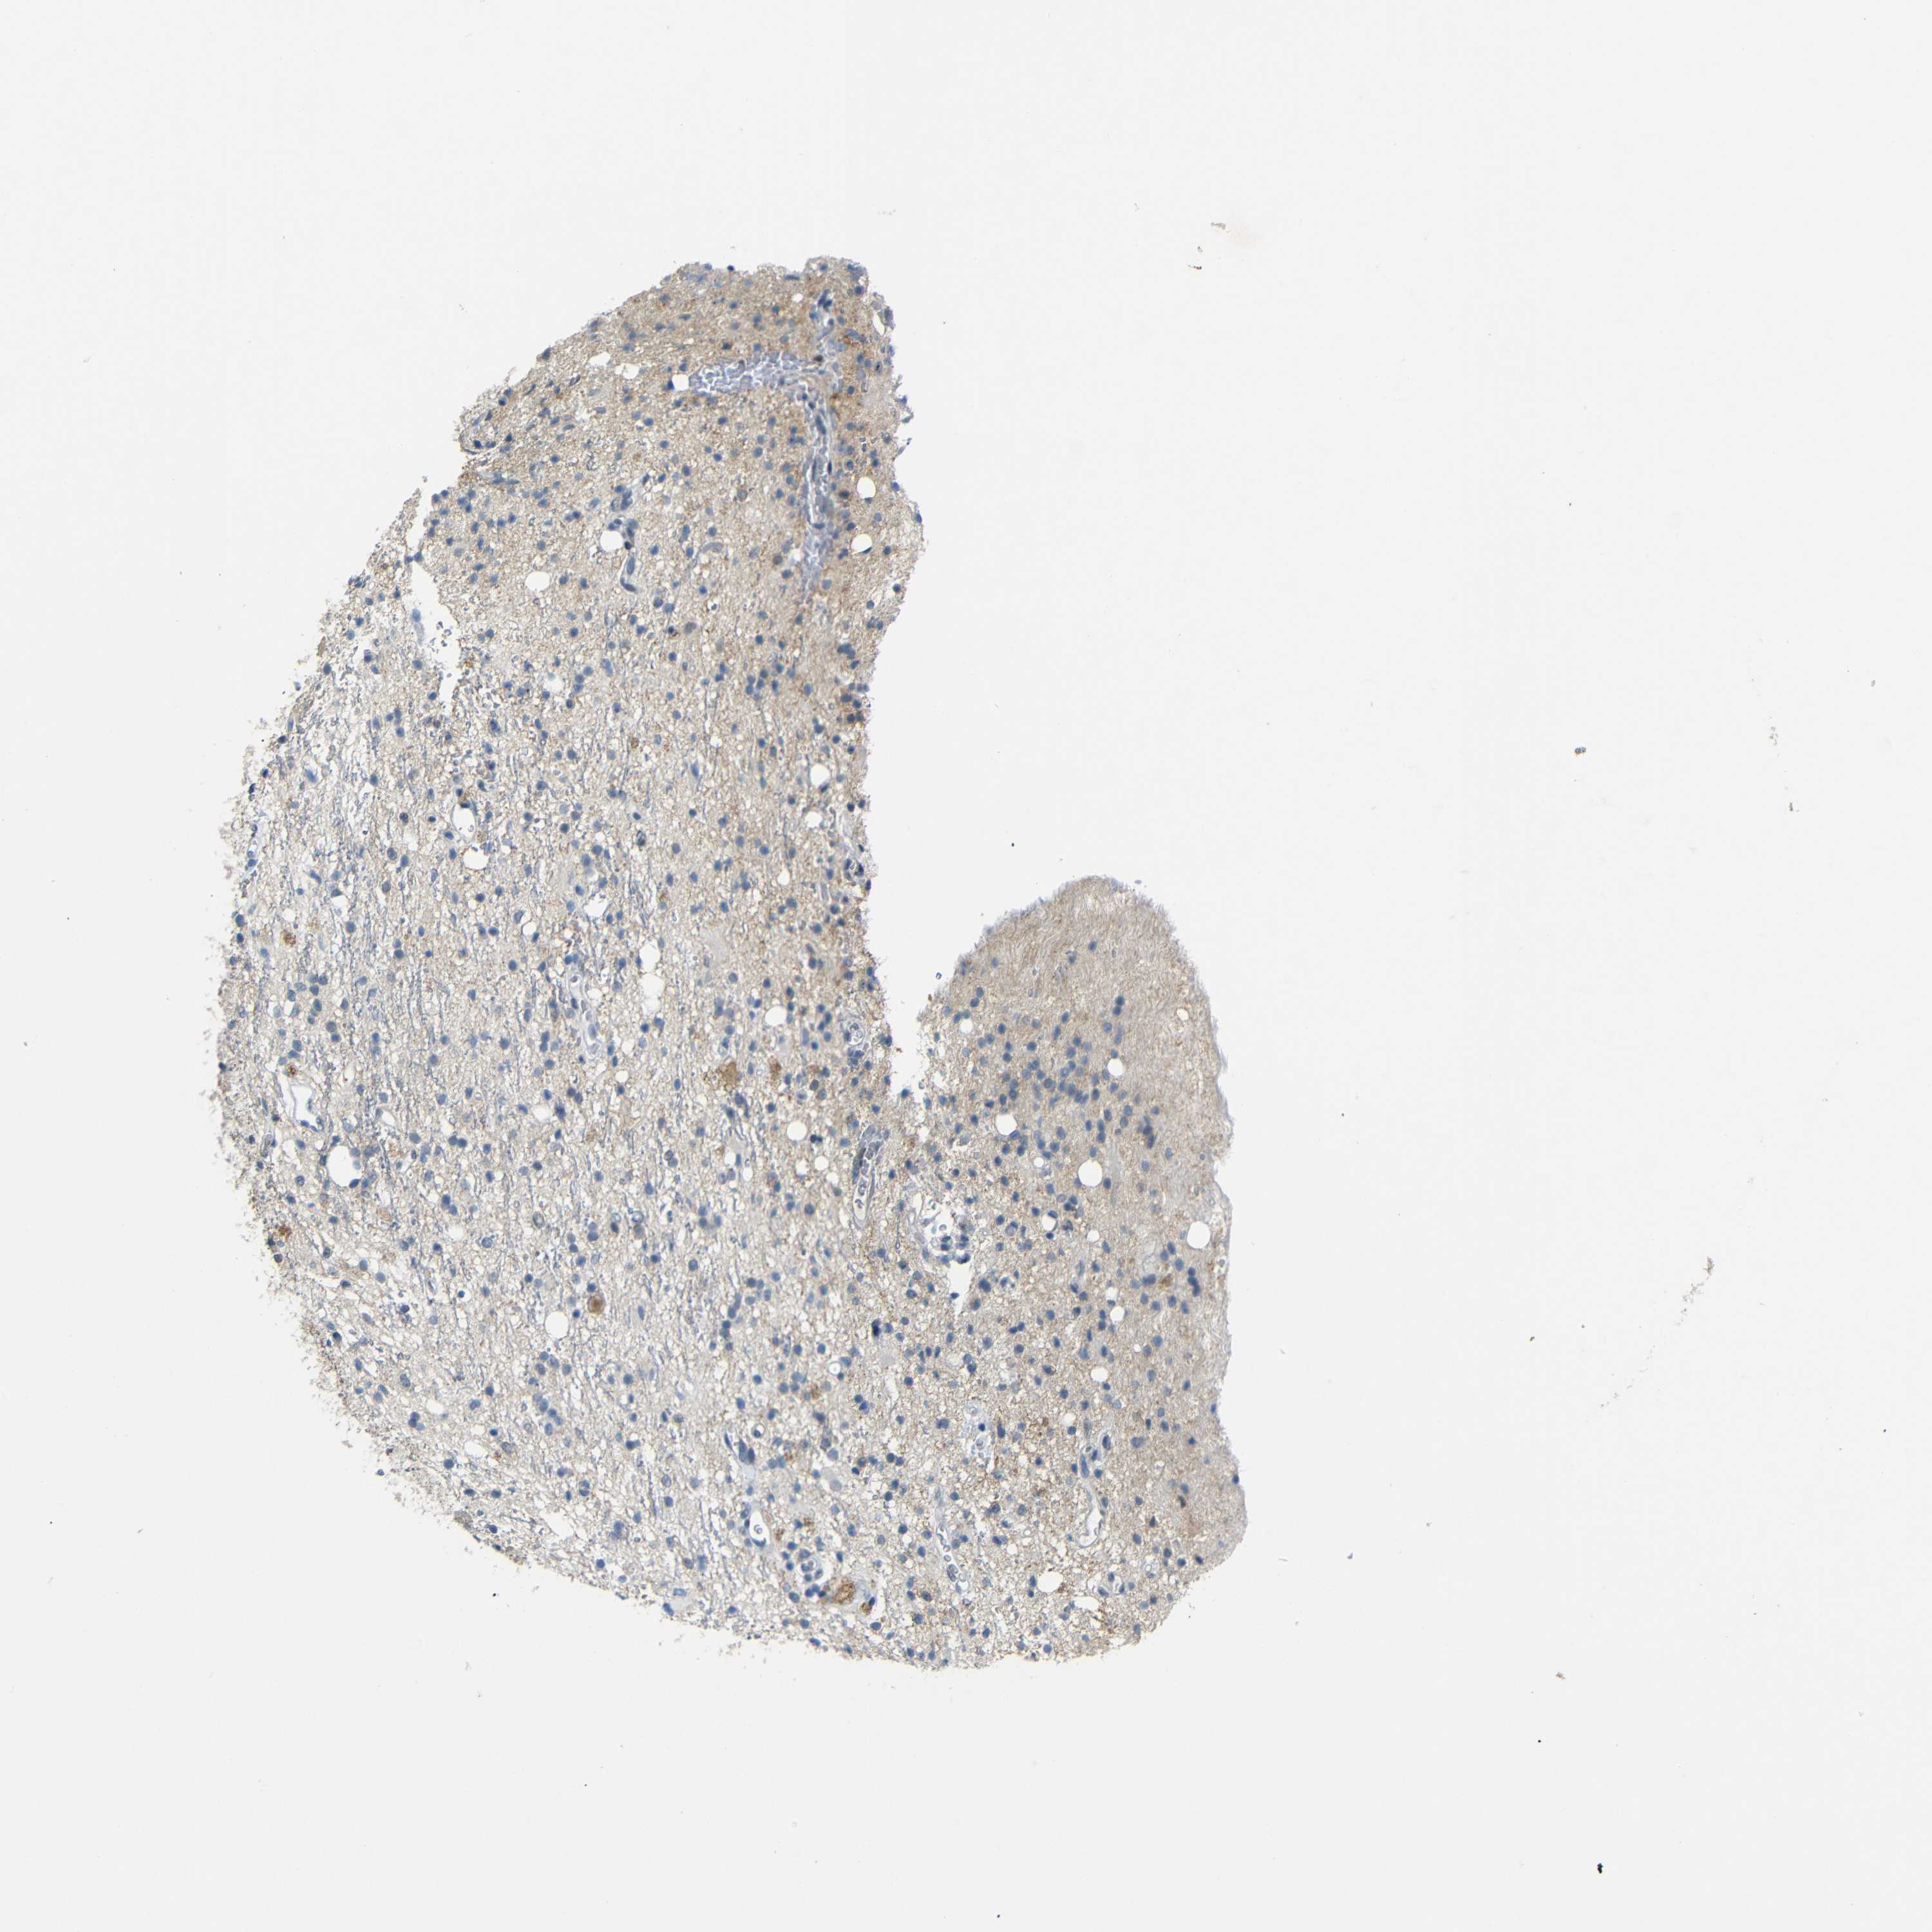

GLIOMA - Protein expressioni

A mouse-over function shows sample information and annotation data. Click on an image to view it in a full screen mode. Samples can be filtered based on level of antibody staining by selecting one or several of the following categories: high, medium, low and not detected. The assay and annotation is described here.

Note that samples used for immunohistochemistry by the Human Protein Atlas do not correspond to samples in the TCGA dataset.

Antibody stainingi

Antibody staining in the annotated cell types in the current human tissue is reported as not detected, low, medium, or high, based on conventional immunohistochemistry profiling in selected tissues. This score is based on the combination of the staining intensity and fraction of stained cells.

Each image is clickable and will lead to virtual microscopy that enables deeper exploration of all samples and also displays staining intensity scores, fraction scores and subcellular localization as well as patient and tissue information for each sample.

Antibody HPA013185

Staining

High

Medium

Low

Not detected

Intensity

Strong

Moderate

Weak

Negative

Quantity

>75%

75%-25%

<25%

None

Location

Nuclear

Cytoplasmic/membranous

Cytoplasmic/membranous,nuclear

Glioma, malignant, High grade

Glioma, malignant, Low grade